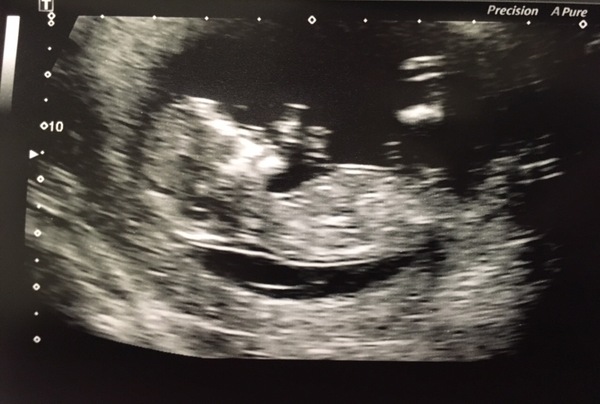

I had my scan today and utterly relieved to see that wee manatee jumper my about! It's such a lovely experience to see it waving its wee arms and touching its face. I cried, it was totally unexpected 😂

Date was confirmed bang on what I had. Congratulations to all the other scans today and yesterday and all the best for those still waiting x x x

Loving all the lovely scan pics

skee lovely picture. I didn't cry, which surprised me. Told everyone in work this afternoon and only cried cos one of my colleagues cried!